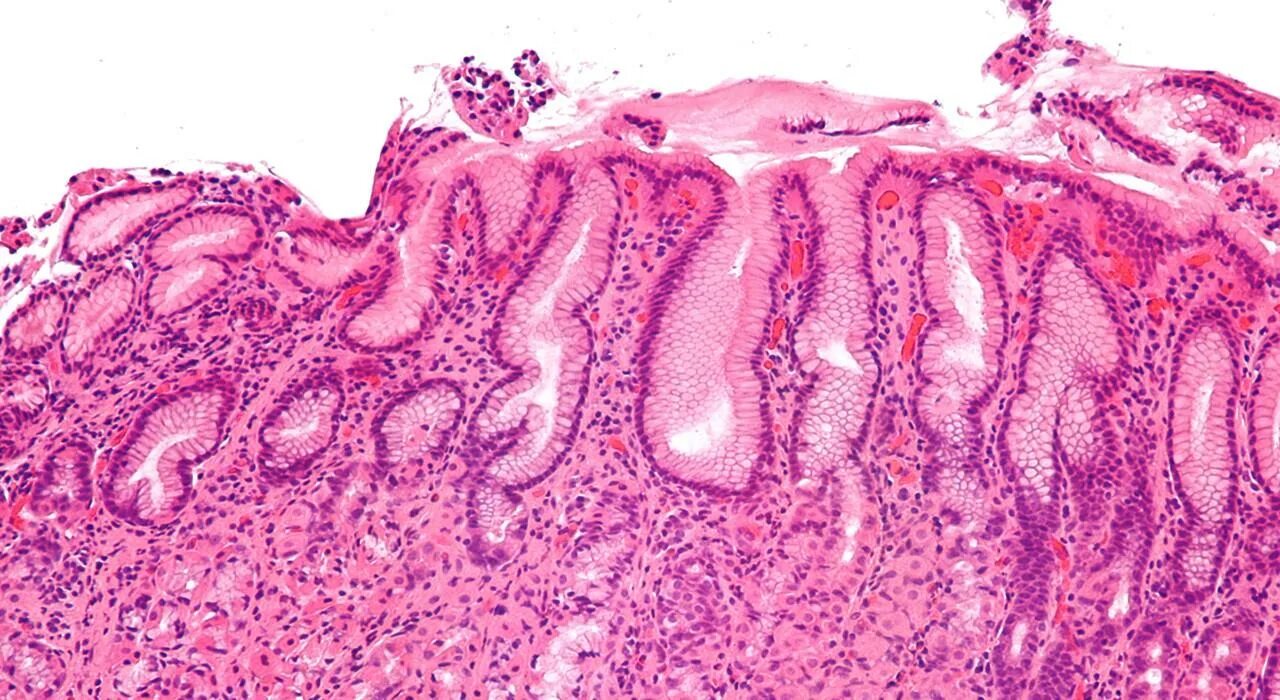

Острый гастроэнтерит формы